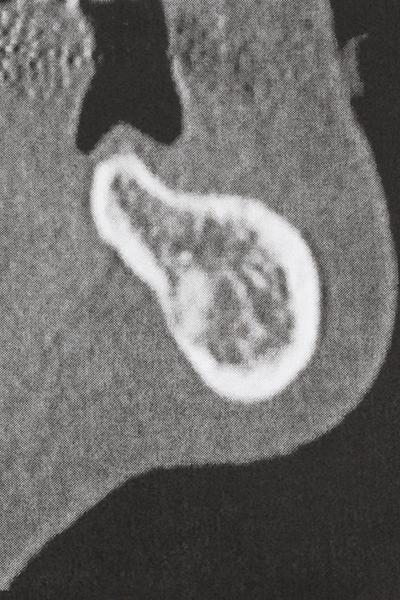

Wie sich in der Vergangenheit gezeigt hat stellt prinzipiell jeder knochenchirurgische Eingriff eine mögliche Indikation für die Piezochirurgie dar. So lässt sich die Präparation des mobilen Segmentes bei der Distraktionsosteogenese (Abb. 23-25) und der Sandwichosteotomie mit speziellen Ansätzen bewerkstelligen, ohne die für den Erfolg beider Techniken essenzielle Blutversorgung des krestalen Anteils zu gefährden (Gonzalez-Garcia, Diniz-Freitas et al. 2008).

Weitere Einsatzgebiete ergeben sich in der Kieferhöhlenchirurgie: Hier können nach konzentrischer Präparation eines in der Regel trapezförmigen Knochendeckels der fazialen Kieferhöhlenwand Pathologien und Fremdkörper aus der Kieferhöhle entfernt werden. Der Knochendeckel wird nach Abschluss des intra-antralen Operationsanteils reponiert und durch Verkeilen oder adaptierende Nähte gegen Dislokation gesichert.

Rein kieferchirurgische Indikationen ergeben sich unter anderem in der orthognathen Chirurgie, bei der Genioplastik (Abb. 27-30) sowie der Orbitadekompression bei Patienten mit fortgeschrittener endokriner Orbitopathie bei Morbus Basedow (Ponto, Zwiener et al. 2014). Zudem finden Piezogeräte je nach Klinik Anwendung in der kraniofazialen Chirurgie sowie bei der Entfernung von Schädelbasistumoren.